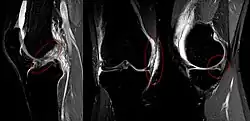

MRI images of Unhappy triad from left to right: ACL, MCL, medial meniscus.

In 1936, Cambell stated that an "impairment of the anterior crucial and medial ligaments is associated with injuries of the internal cartilage". In 1950, O'Donoghue described the unhappy triad as: (1) rupture of the medial collateral ligament, (2) damage to the medial meniscus and (3) rupture of the anterior cruciate ligament. O'Donoghue estimated the incidence rate in the traumatic sports knee to be 25%.[3]